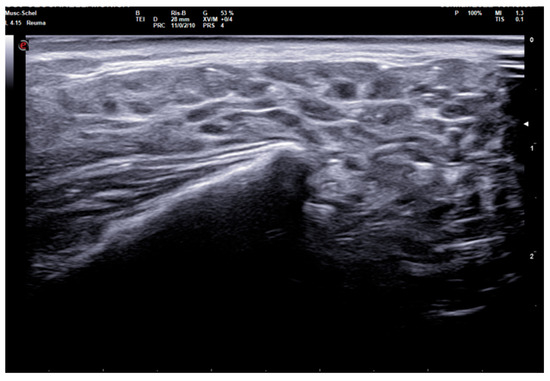

The 0–3-graded OMERACT score was used to assess the ultrasonographic structure of each gland [13,14,15]. The score was applied on each gland, and defined as follows: Grade 0, normal parenchyma (sono-structure comparable to the thyroid gland); Grade 1, mild inhomogeneity without anechoic or hypoechoic areas and hyperechogenic bands; Grade 2, moderate inhomogeneity with focal anechoic or hypoechoic areas; and Grade 3, severe inhomogeneity with diffuse anechoic or hypoechoic areas occupying the entire gland surface [13] (Figure 1).

Figure 1. Parotid SGUS score 3 in primary Sjogren syndrome. Female 51-year-old patient with sicca syndrome, positive Schirmer test, positive autoimmunity (ANA+, Ro-SSA+), positive labial biopsy for SS. A coronal trasverse scan over left parotid (4–15 MHz linear probe) shows diffuse inhomogeneity with hypo-anechoic areas occupying the entire gland volume, surrounded with septal echoic thickening and scanty normal parenchymal tissue (SGUS-OMERACT score = 3).